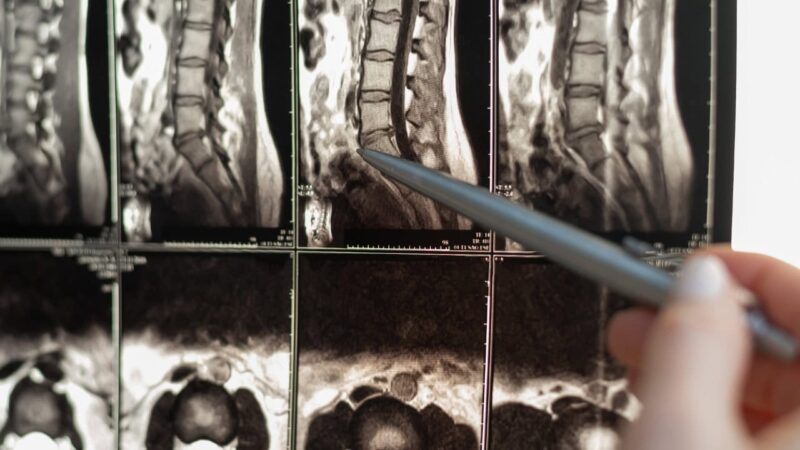

En algunos casos, las neuropatías por atrapamiento surgen en la columna vertebral, como en las radiculopatías cervicales o lumbares. Estas afecciones se producen cuando las raíces nerviosas se comprimen, a menudo debido a hernias discales o cambios degenerativos en la columna vertebral. Aunque estos trastornos puedan parecer distintos, comparten el mecanismo subyacente de la compresión o irritación nerviosa, que provoca diversos síntomas sensoriales y motores.

7. Pruebas diagnósticas

Las herramientas diagnósticas avanzadas, como la resonancia magnética y el electrodiagnóstico, son útiles para confirmar el diagnóstico en casos complejos. La resonancia magnética es útil para identificar cambios estructurales en los tejidos que provocan neuropatías, mientras que los estudios de conducción nerviosa pueden evaluar el estado funcional de los nervios afectados.ars y suele acompañarles a lo largo de sus años productivos. Este momento plantea un reto importante, ya que las migrañas se experimentan predominantemente cuando las personas suelen estar centradas en sus carreras, el trabajo y la crianza de los hijos. Tras alcanzar este pico, muchas personas experimentan un descenso gradual de la frecuencia de las migrañas a medida que envejecen, especialmente las mujeres, que pueden notar una reducción de las migrañas en torno a la menopausia.

El futuro del diagnóstico y tratamiento de la neuropatía por atrapamiento es prometedor, gracias a los avances en diagnóstico por imagen y medicina de precisión. La RM de campo ultraalto y la neurografía por RM están allanando el camino hacia diagnósticos más precisos al permitir a los médicos visualizar los nervios con un detalle sin precedentes. Estas técnicas son especialmente valiosas para identificar cambios sutiles en la estructura nerviosa que pueden no ser visibles con las imágenes tradicionales.